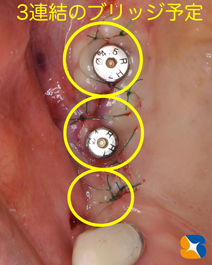

無事に施術が完了しました。

傷口がキレイに治れば、早々に型取りをして仮歯を装着予定にしています。

年内には奥歯が復活しますのであと少しお待ちください。

使用インプラント:USAオッセムSA 直径5㎜と6㎜、長さ10㎜

手術から3ヶ月後の様子です。

手術から4ヶ月後の様子です。